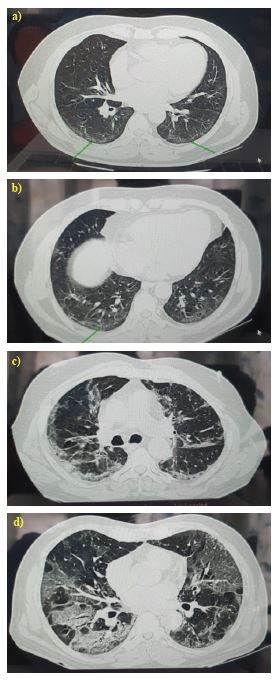

The various radiological patterns observed among the patients are illustrated in Figure 1.

Recent studies have reported that most patients with COVID-19 disease exhibit typical radiologic features on chest CT scans. These features commonly include bilateral ground-glass opacities in the lower lobes, with a posterior or peripheral distribution, which progress to a crazy-paving pattern and eventually to areas of consolidation.8 Moreover, imaging results can be used to evaluate the disease's prognosis and severity, assisting physicians in timely clinical decision-making. Therefore, this study was undertaken to fill the lacunae in the current literature.

The CT images were analysed by the investigators to identify typical features of COVID-19 pneumonia, which include subpleural unilateral or bilateral ground-glass opacities (GGOs) in the lower lobes with a peripheral or posterior distribution. These findings may progress to a crazy-paving pattern and subsequently to consolidation.10 Taking into account the degree of anatomic involvement, a semiquantitative CT severity score, as suggested by Pan et al.,was determined for each of the five lobes.10,11